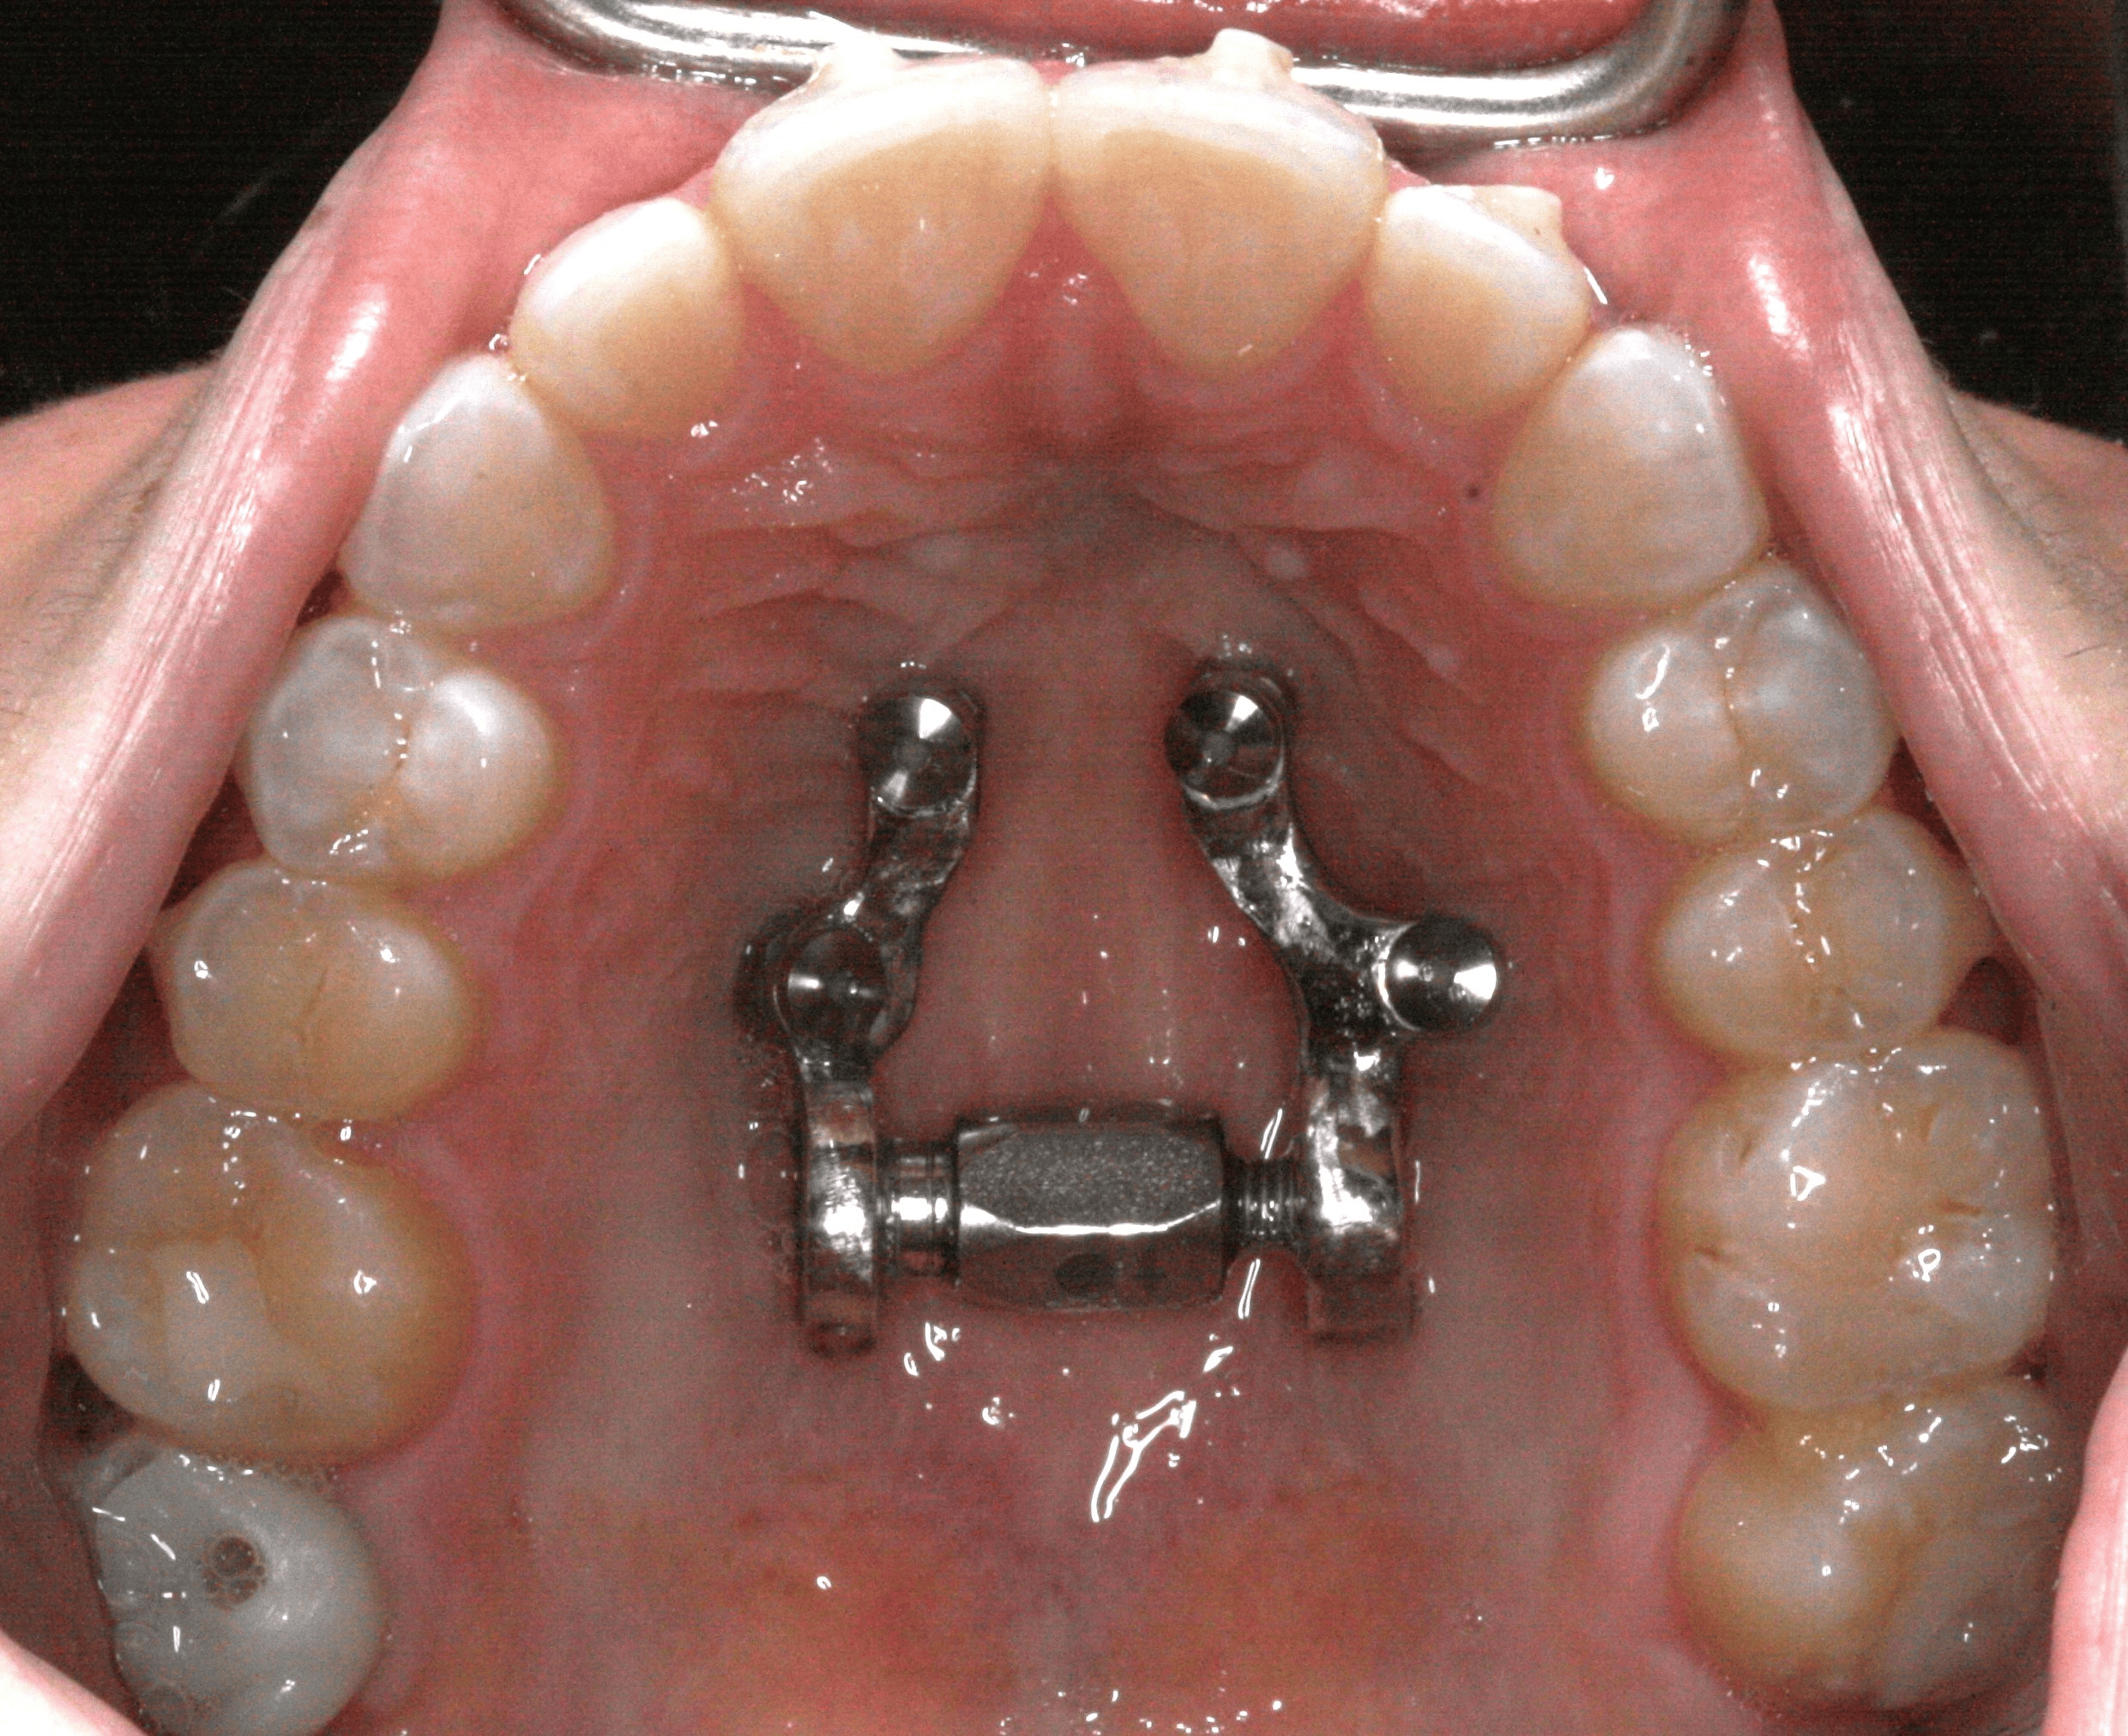

MASPE zero is a customized, miniscrew-assisted slow palatal expansion system designed for controlled skeletal widening in adult and non-growing patients. Built on a fully digital workflow and paired with clear aligner therapy, it promotes true skeletal change while minimizing dental tipping and midline diastema.

- True skeletal expansion with controlled, gradual activation

- Integrated aligner therapy to minimize midline diastema

- Designed specifically for adult and non-growing patients